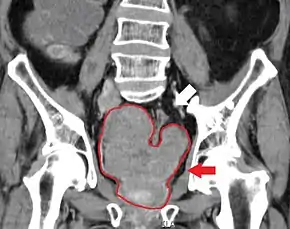

Imaging

Ultrasound and magnetic resonance imaging (MRI) are the two main imaging methods used for prostate cancer detection.

MRI Organ-confined prostate cancer

Bony metastases from prostate cancer

The most important distinction made by any staging system is whether the cancer is confined to the prostate. In the TNM system, clinical T1 and T2 cancers are found only in the prostate, while T3 and T4 cancers have metastasized. Several tests can be used to look for evidence of spread. Medical specialty professional organizations recommend against the use of PET scans, CT scans, or bone scans when a physician stages early prostate cancer with low risk for metastasis.[95] Those tests would be appropriate in cases such as when a CT scan evaluates spread within the pelvis, a bone scan looks for spread to the bones, and endorectal coil magnetic resonance imaging evaluates the prostatic capsule and the seminal vesicles. Bone scans should reveal osteoblastic appearance due to increased bone density in the areas of bone metastasis—the reverse of what is found in many other metastatic cancers.

Sclerosis of the bones of the thoracic spine due to prostate cancer metastases (CT image)

Sclerosis of the bones of the pelvis due to prostate cancer metastases